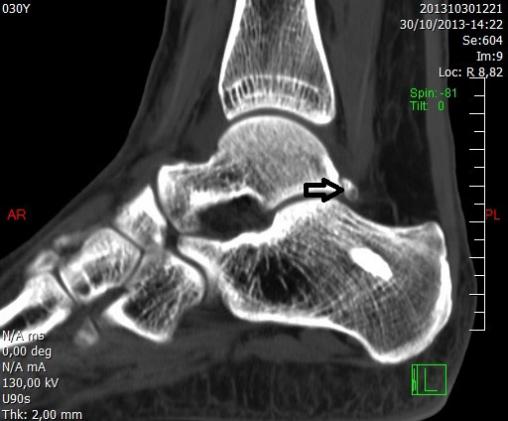

Collection P. Frances La TDM met en évidence un fragment osseux triangulaire surnuméraire : le trigone (flèche). Cette anomalie congénitale est due à l’absence de soudure du versant postérieur de l’astragale, qui devrait avoir lieu vers l’âge de 12 ans.